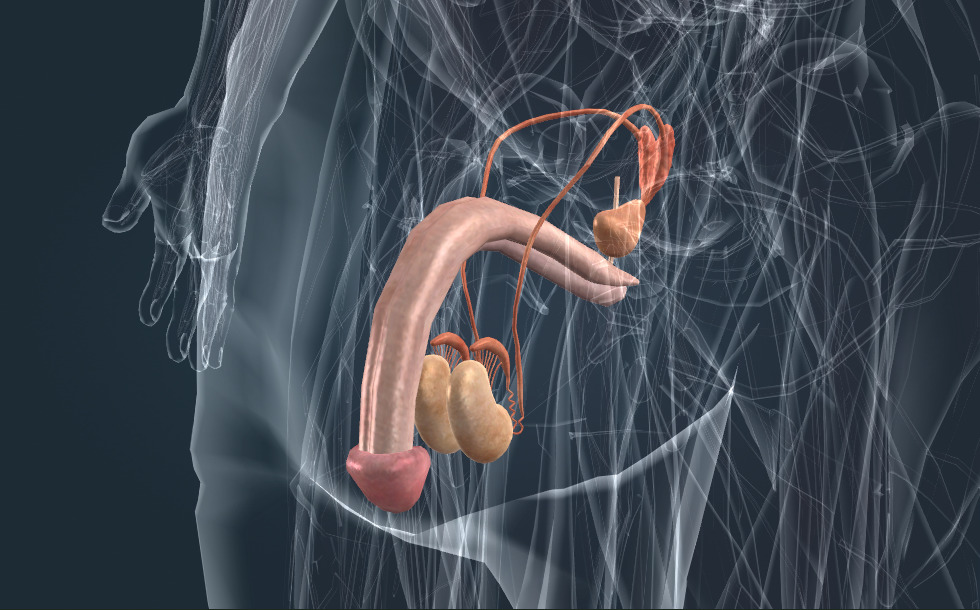

Voortplantingsorganen

- testikel - Het produceert sperma en het hormoon testosteron (mannelijk geslachtshormoon), wat de rijping van sperma en de ontwikkeling van een mannelijk figuur en lichaamsbeharing stimuleert.

- bijbal - Slaat het sperma op dat geproduceerd wordt in de testikels (teelballen).

- zaadleiders

- zaadblaasjes - Het speelt een belangrijke rol bij de vorming van zaadcellen.

- prostaat - Het speelt een belangrijke rol bij de vorming van zaadcellen. Staat ook bekend als de prostaat.

De geslachtsorganen zijn verantwoordelijk voor de voortplanting. Deze produceren gameten. Tijdens de bevruchting smelt het eitje samen met een spermacel en vormen ze samen een zygote die zich later tot een embyro ontwikkelt. De reproductieve klieren bij de man zijn de testikels (teelballen) die sperma produceren. Sperma wordt opgeslagen in de bijbal; tijdens een zaadlozing wordt het zaad uitgestoten samen met sperma via de plasbuis. Het zaad wordt door de prostaat en de zaadblaasjes geproduceerd.

De geslachtsorganen zijn verantwoordelijk voor de voortplanting. Deze produceren gameten. Tijdens de bevruchting smelt het eitje samen met een spermacel en vormen ze samen een zygote die zich later tot een embyro ontwikkelt. De reproductieve klieren bij de man zijn de testikels (teelballen) die sperma produceren. Sperma wordt opgeslagen in de bijbal; tijdens een zaadlozing wordt het zaad uitgestoten samen met sperma via de plasbuis. Het zaad wordt door de prostaat en de zaadblaasjes geproduceerd.